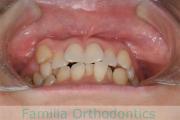

No.21V-042

- 側方偏位

- 叢生

- 39歳

- 女性

- 抜歯部位

- 上:

- 44

- 下:

- 1|8

- 主な使用装置:

- FEA

- 治療にかかった費用:

- 90万円

八重歯を治したい、とのことで来院されました。アゴのズレが大きいこと、親知らずに下の奥歯が一部食い込まれていて保存に不安があったこと、から上の左右小臼歯と下の前歯一本を抜歯してマルチブラケット法を行いました。4年弱、45回程度の通院が必要でした。

上下前歯とも叢生(でこぼこ、凹凸、ガタガタ)が強く、後戻りのリスクのあるケースです。

- ≫治療前

上顎

下顎

- ≫治療後